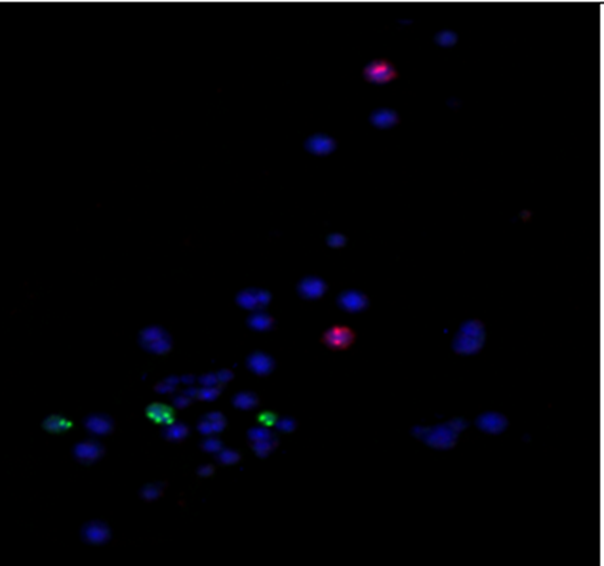

Conventional cytogenetic analysis by GTG banding on bone marrow cells revealed a clonal chromosomal abnormality with a translocation between chromosomes 1 and 12, noted as t(1;12)(q24;q24.1) in 16 out of 20 metaphases. Four metaphases showed a normal male karyotype (46, XY), indicating the presence of both abnormal and normal clones (Figure 1). Whole chromosome painting (WCP) FISH using probes for chromosomes 1 (orange) and 12 (green) demonstrated an abnormal fusion signal pattern indicative of a t(1;12) translocation. Orange fluorescence from chromosome 1 appeared on a predominantly green chromosome 12, confirming the transfer of genetic material between these chromosomes (Figure 2). The abnormal pattern was consistently detected in all 10 analysed metaphases, supporting the presence of a recurrent t(1;12) chromosomal translocation. To confirm the Trisomy of 21 FISH technique was used in which AML_ETO probe was used. AML1 gene is Present on Chromosome 21, which was labelled, with Green Fluorochromes while ETO gene is on Chromosome 8 labelled with Fluorochromes Orange.[ In Figure 3, three green signals indicates the Trisomy 21.

Figure 3: Representative image FISH in which Chromosome 21 was labelled with Fluorochromes green and Chromosome 8 with orange. 3 Green signal indicates trisomy of Chromosome 21.